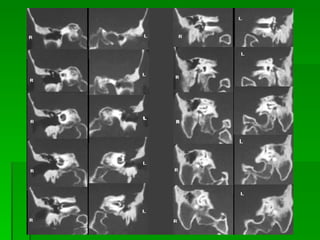

Radiological assessment * Plain radiogram  : it is of value in cholesteat  -omatus cases(shows lytic lesions) ,also it detect variation in anatomic landmarks. * CT-Scan :   CTscanning  performed when:  1. intratemporal or intracranial  complications are suspected  2. surgical intervention being planned 3.to study anatomy of temporal bone These studies should include both axial & coronal fine cuts (1-1.5mm) through the temporal bone.

Evaluation - Audiology  – usually conductive loss. - Imaging   * CT temporal bone   :  for  -revision cases  -complications of chronic suppurative otitis media  -sensorineural hearing loss  -vestibular symptom  -other complications of cholesteatoma

Radiological assessment *Plain radiogram : it is of value in cholesteat -omatus cases(shows lytic lesions) ,also it detect variation in anatomic landmarks. * CT-Scan : CTscanning performed when: 1. intratemporal or intracranial complications are suspected 2. surgical intervention being planned 3.to study anatomy of temporal bone These studies should include both axial & coronal fine cuts (1-1.5mm) through the temporal bone.